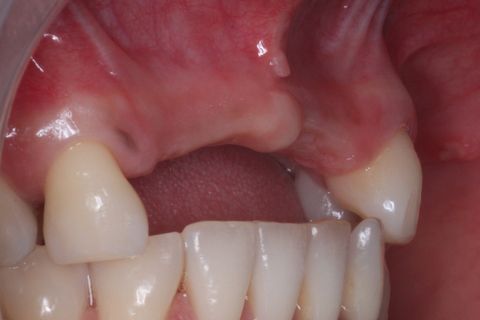

Foto Inicial. Paciente fazendo uso de Prótese Parcial removível.

Foto Oclusal superior sem a Prótese Parcial removível

Foto oclusal aproximada, realçando o defeito ósseo na região vestibular